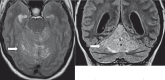

Lhermitte-Duclos disease is a rare pathologic condition consisting of a dysplastic gangliocytoma of the cerebellum. Its association with phacomatosis and an autosomal dominant neoplastic syndrome, Cowden's syndrome is also known. Modern neuroimaging contributes to a correct diagnosis and pre- and postoperative evaluation. Here we describe the morphologic and metabolic aspects of the disease as shown by conventional MRI, diffusion imaging and spectroscopy in a 31-year-old woman. In addition, the specific neuroradiologic characteristics are presented and discussed in the light of the main pathologic and clinical features, such as hypertrophy of the cerebellar folia associated with white matter atrophy.